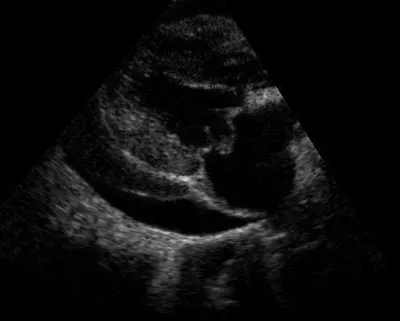

Figure 2: Pericardial effusion diagnosed with TFAST examination

Featured Image